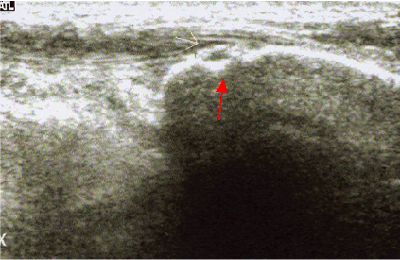

Esostosi falangea esostosi falangea